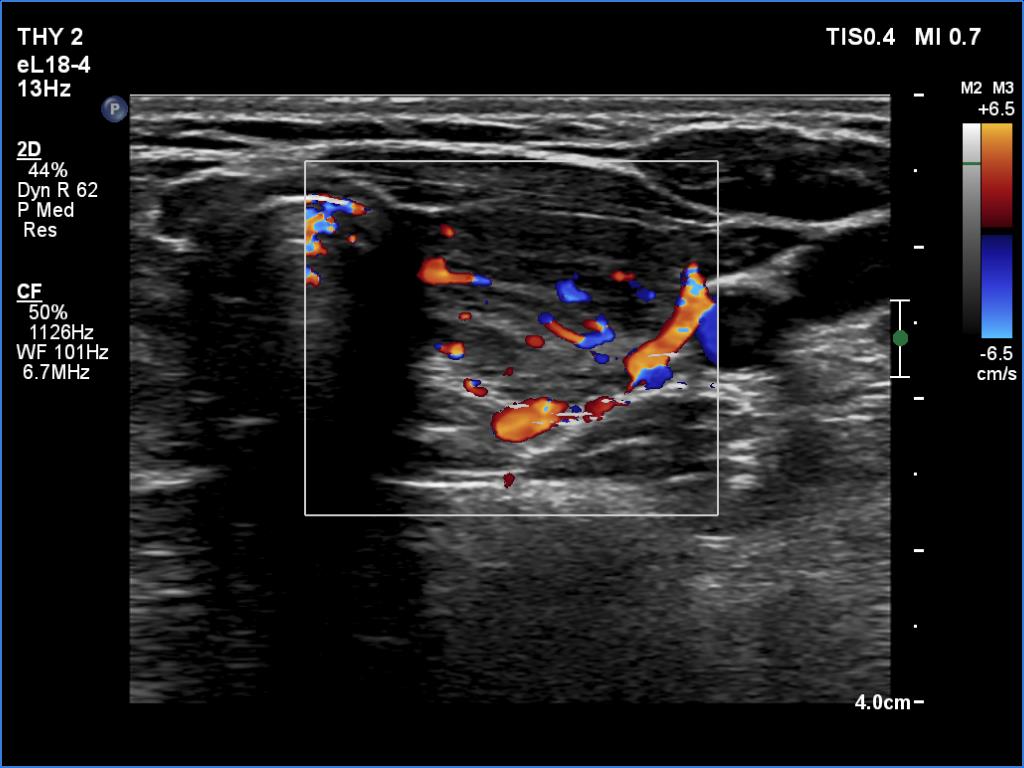

Left lobe, transverse scan, color Doppler mode. The vascularization is average.